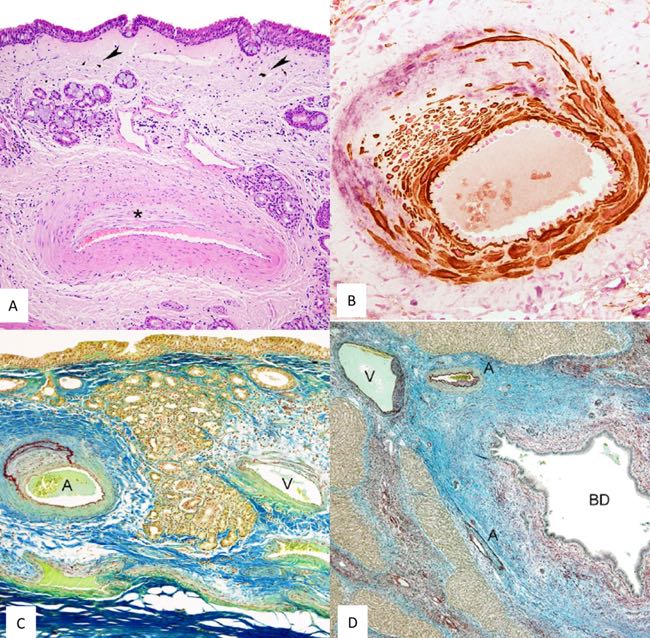

In the nasal cavity, lesions predominated in small arteries close to the epithelial surface. Many vessels showed eccentric intimal proliferation with variable oedema and fibrosis of the surrounding mucosa, without evidence of inflammation or calcification. Immunohistochemistry confirmed degenerative arterial changes, particularly in arteries within the alar folds and oriented towards the epithelial surface. Sheep with more severe hepatic lesions showed a higher proportion of affected nasal arteries (Figure 6).

Figure 6. Microscopic lesions and immunohistochemistry exam. A. Histopathology of the nasal mucosa. Small artery located close to the surface of the nasal mucosa. Nasal epithelium remains unaltered. Intima of the artery shows eccentric proliferation (asterisk). Edema and fibrosis together with small groups of mononuclear cells, few neutrophils and melanotic cells are present (arrowheads). Hematoxylin-eosin. B. Immunohistochemistry of the nasal mucosa arteries. Small artery with intense intimal proliferation of smooth muscle cells and collagen III. Smooth muscle cells are shown with brown labeling and collagen III with light purple. Double immunohistochemistry smooth muscle actin and collagen III. C. Histopathology of the arteries of the nasal mucosa. Nasal mucosa showing one artery with intense intimal proliferation together with herniation and duplication of internal elastic membrane (A). Vein showing minimal changes in the wall (V). Orcein-Cajal's picrocarmin combination D. Histopathology of the liver. Interlobular septum showing 1 vein (V), 2 arteries (A) and 1 biliary duct (BD). Arteries and vein show sclerosis and intense fibrosis with proliferation of collagen and elastic fibers of interlobular septa. Intima vascular degenerative lesions are orientated to damaged BD. There are few mononuclear cells, mostly surrounding dilated biliary duct. Orcein-Cajal's picrocarmin combination (De las Heras et al., 2022).